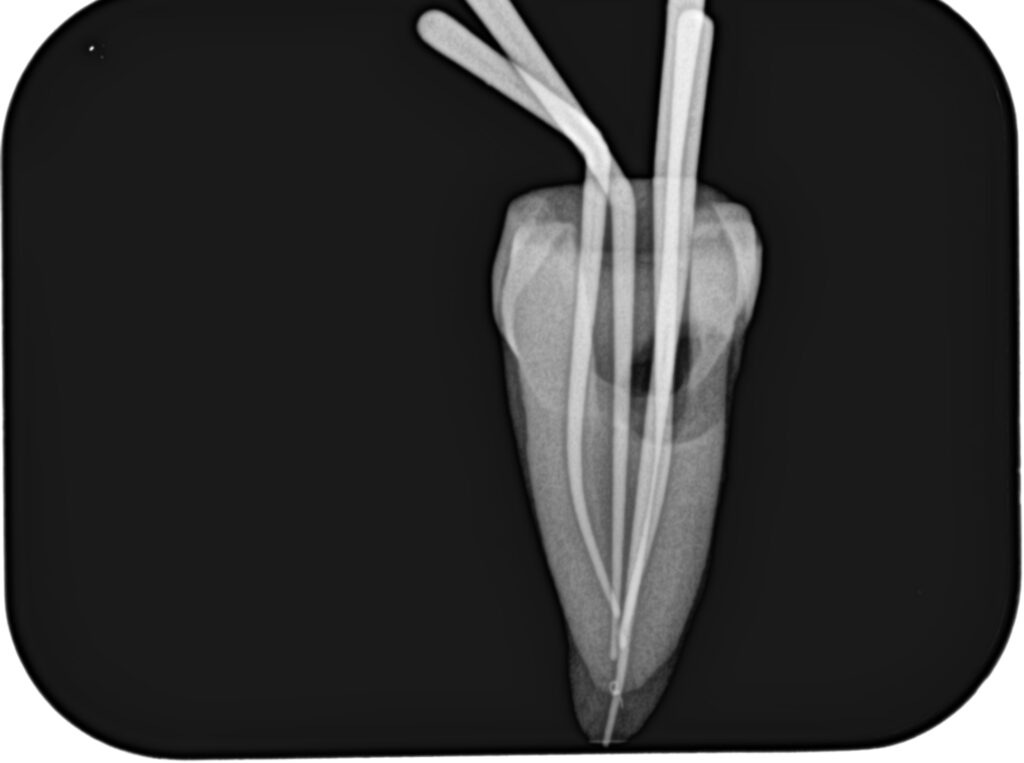

まず作業長の測定方法を行うまでを解説した。

その後、根管形成である。

自分が使用したいFileを使用したが作業長までいかない(特にHyFlex EDM#25が作業長までいかないことが多い)、番手を下げることが多いがどうしたらいいか?

上記動画では、細い穿通させた根管を号数を下げずにWave One Gold #25だけで作業長まで形成している。